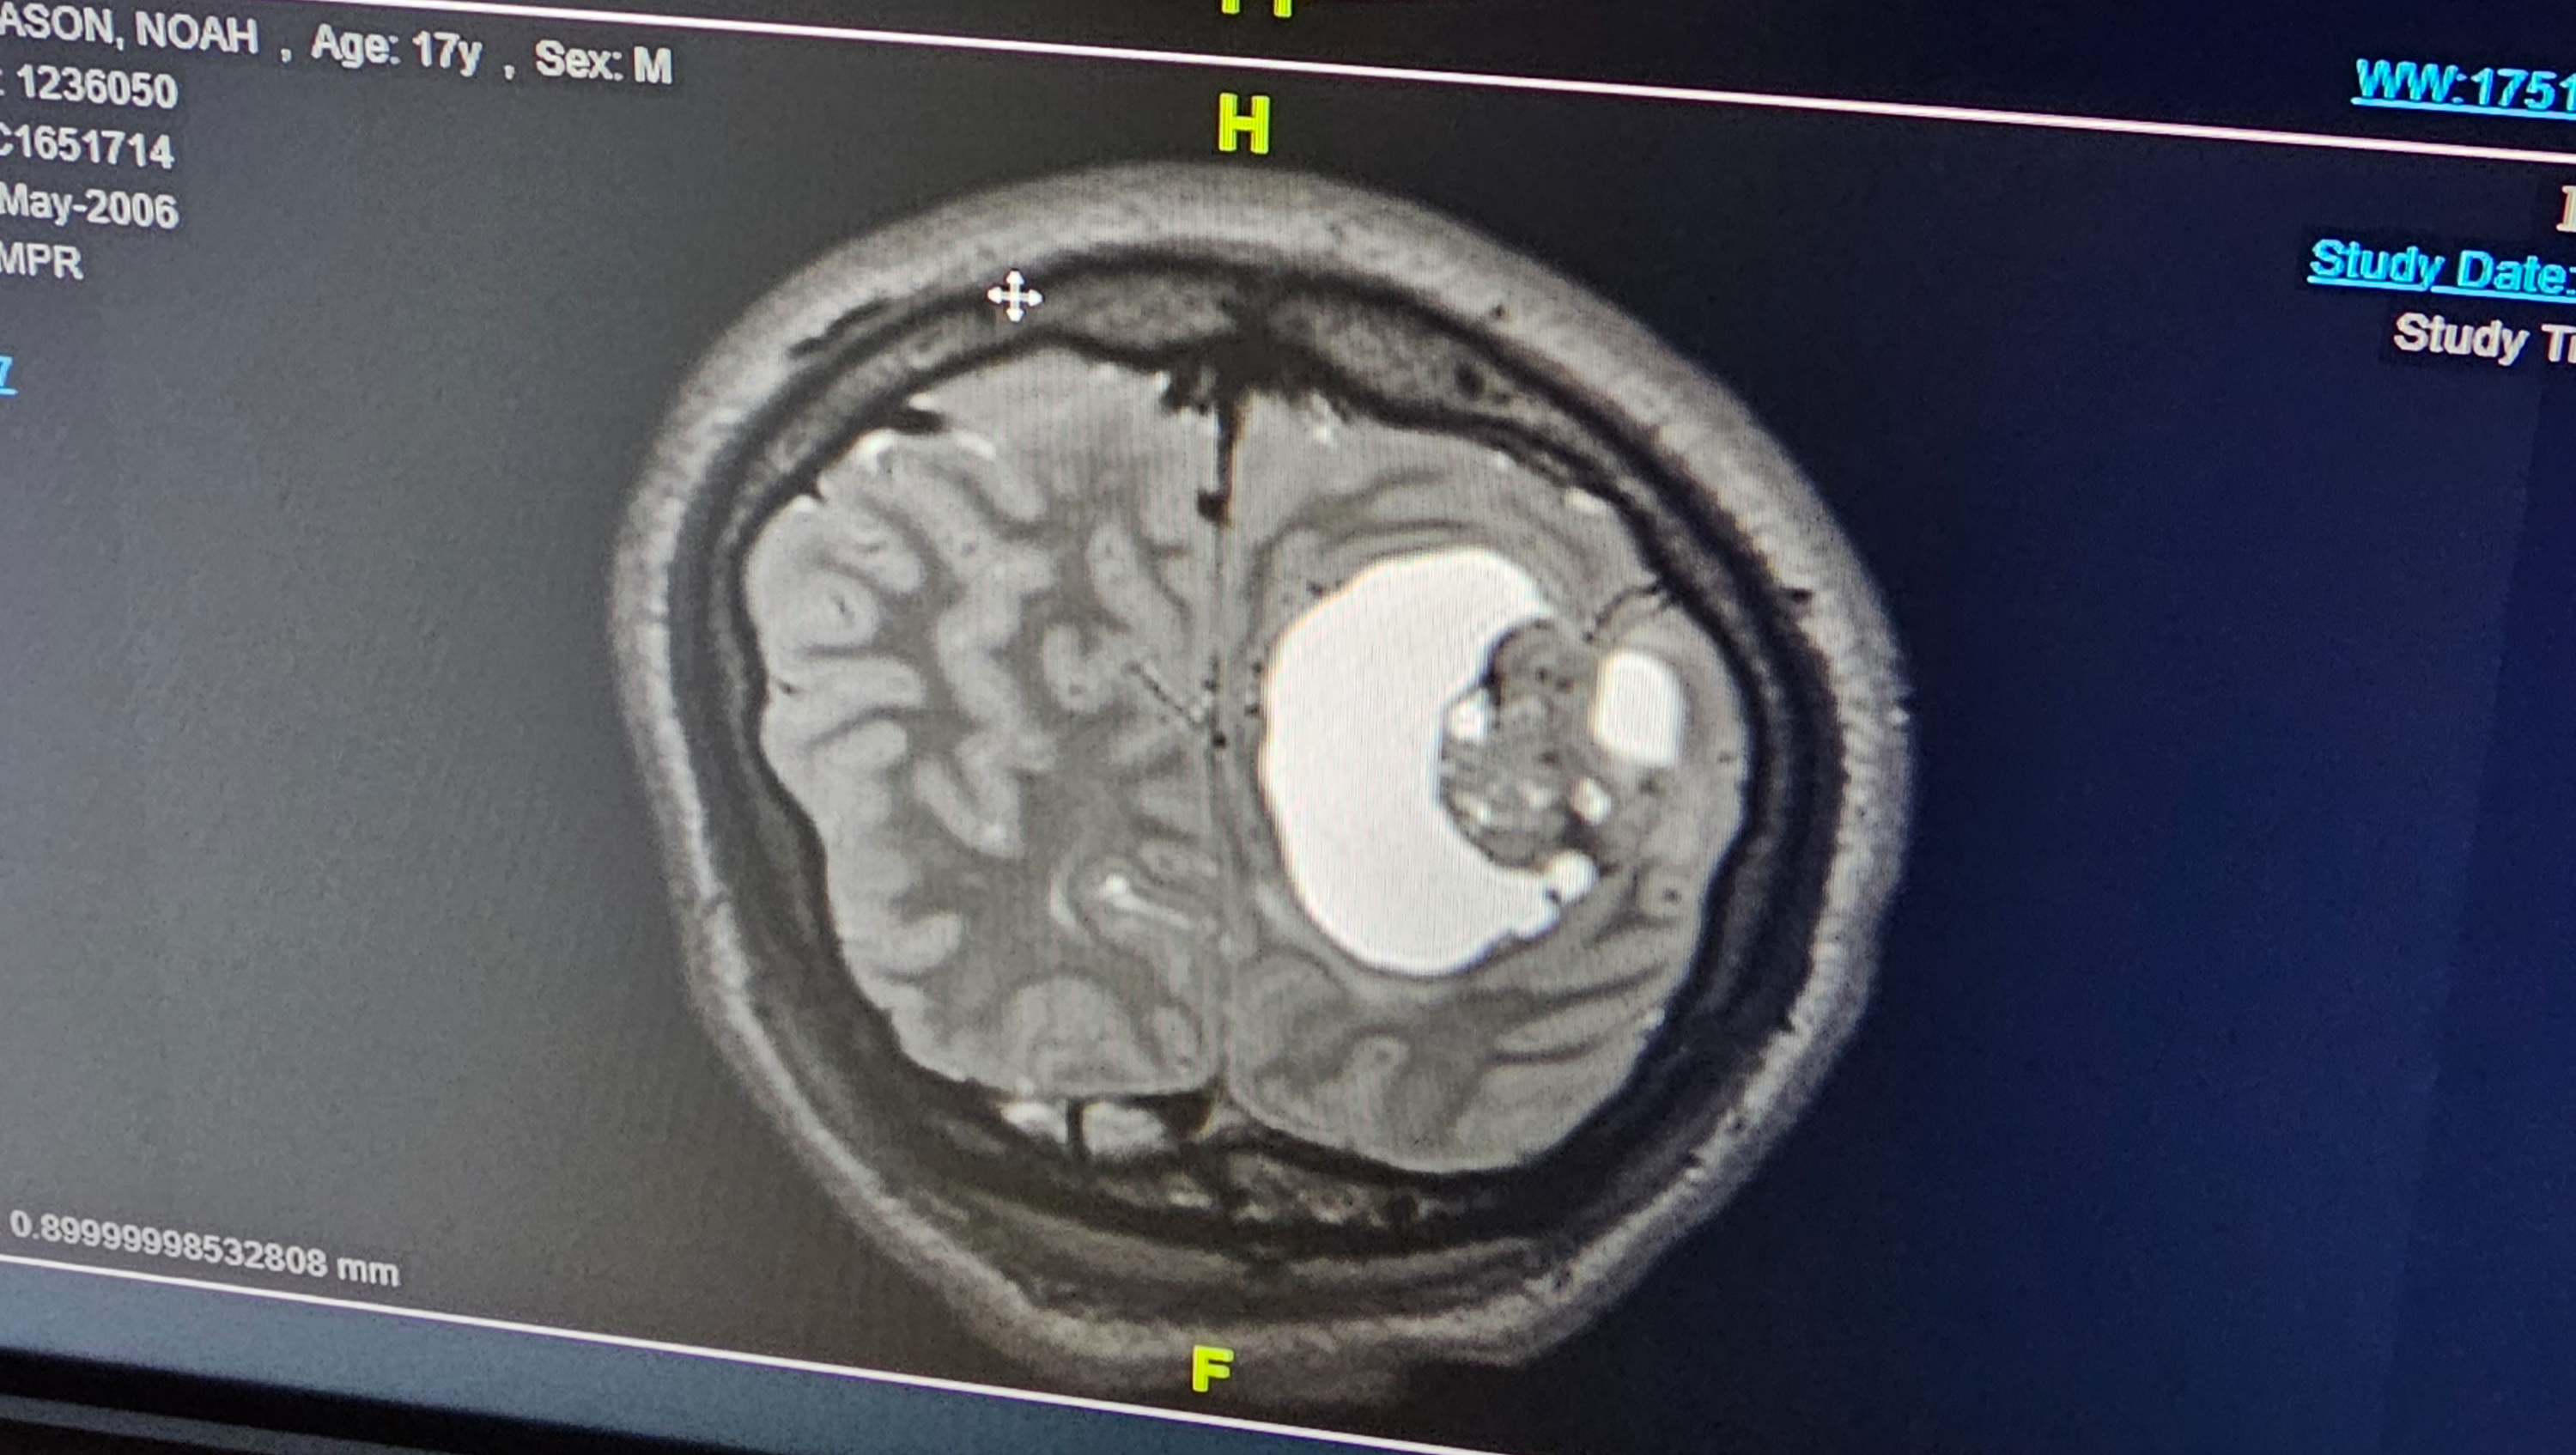

It started when Mason was complaining of having headaches...that would not completely go away. It got better at times, but it came to the point where I had to take him to the hospital because he was telling me something was wrong. The hospital gave him the classic migraine cocktail and sent us home. A couple more days go by and Mason wants to go to the hospital again- insisting, saying that something is not right. So i demanded the hospital did something- not medicine- but look at his head, to see if something was wrong. They did a CT-scan, and the unimaginable results came back- he had a tumor in his brain. We were surprised because you never expect that in a healthy 17 year old. At that point they gave us an envelope with specific instructions to go straight to Akron Childrens Hospital. We spent the night and first thing the next morning they did a very detailed MRI- full scan with function so they could better understand exactly what was there in his brain. Within 24hrs we were in brain surgery, having this large tumor removed. 20 staples and 5 sleepless nights in the hospital, only to be told to wait for the biopsy results even longer. Our experience at Akron Childrens Hospital was best case scenario for the situation tho- having a great Neurologist and amazing team of specialists. So we waited- an entire month before we got the call. They explained that we needed to come to the hospital, Mason included to go over what they found. I was not prepared for what they would tell us....

PLEOMORPHIC XANTHOASTROCYTOMA! A very rare type of brain cancer with less than 100 cases a year! I held it all together up until that day. We came home, I waited until I could be alone and away from anyone, and I fell apart. As a mother- u never want your children to suffer, to be in pain, to go through anything remotely close to something like brain cancer.